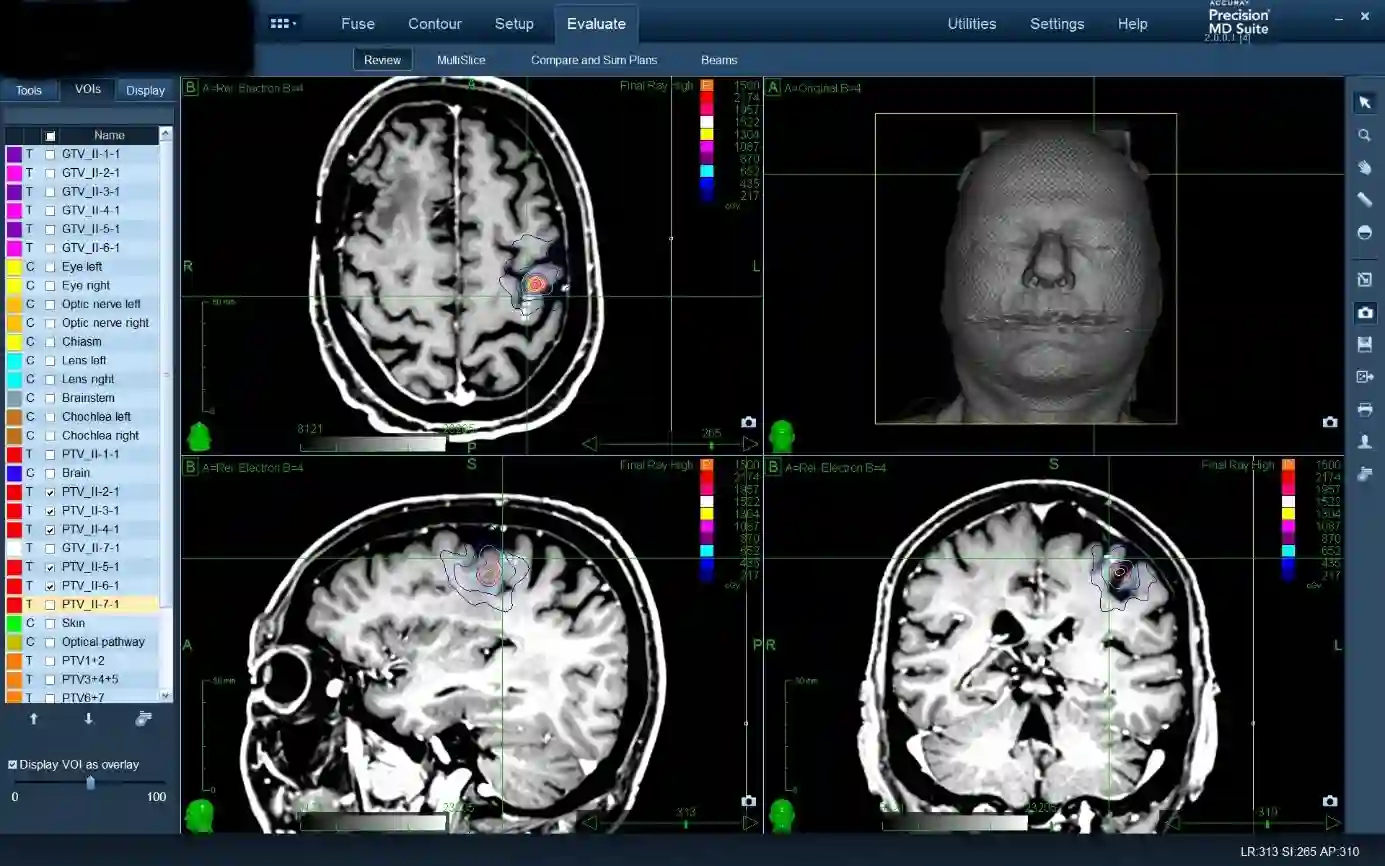

Planung einer radiochirurgischen Behandlung einer Hirnmetastase.